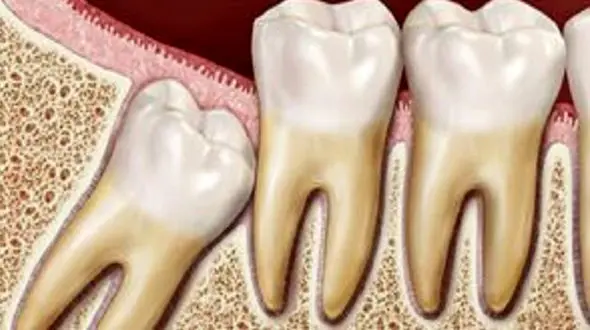

دندان عقل که آخرین دندان در دهان با بلند ترین ریشه است، از جمله دندان هایی است که در صورت آسیب زندگی را برای افراد سخت می کند. این دندان بین سنین 17 تا 25 سالگی در دهان افراد می روید و نگهداری از آن…

رکنا: دندان عقل آخرین سری از دندانهای آسیاب است. زمانی که دندان عقل رشد کرده و از لثه بیرون میزند، علاوه بر ایجاد درد و ناراحتی، سایر دندانها را نیز تحت تأثیر قرار داده و موجب بهم ریختگی آنها میش…